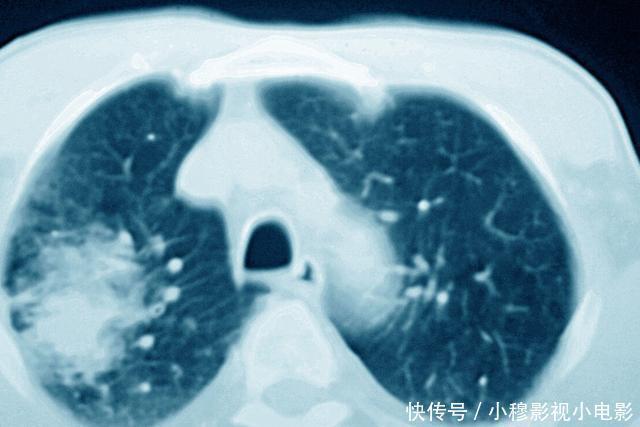

文章插图

另外,有的癌症可能一开始没有办法手术,但是可以先通过放化疗,把病灶缩小,然后再进行手术治疗,那么这其中也是需要通过CT检查来评估病灶情况,了解是否可以手术。